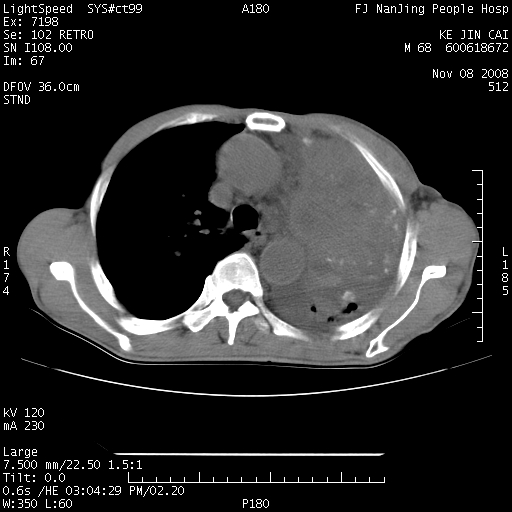

是个很有看头的病例,咋人气那么不旺?没多少人兴趣呢?这个病例几大怪:1   恶性肿瘤侵犯心肌左房怪,心肌一般不会被恶性肿瘤侵犯吧?2   左下肺均匀实变怪,内无含气,有别一般不张实变,含气肺泡完全为液体取代,而非一般不张实变的肺萎陷,冷不丁还以为是肿大的脾脏3   肿瘤本身怪,像tb肺不张4   这么有看头的病例没人气怪。呵呵。

左肺恶性肿瘤侵犯肺动脉,左心房内瘤栓,胸膜转移。

左肺恶性肿瘤侵犯肺动脉,左心房内瘤栓,胸膜转移,少见,学习了。